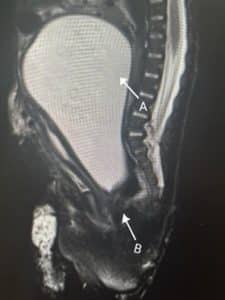

Management of the neonate: A live baby girl was delivered with Apgar scores of 8/10 at 1 minute and then 10/10 at 5 minutes. Baby passed urine almost immediately from a patent urethra. The genitals appeared normal. The neonate had fully developed extra digits on the right hand and right foot. The extra digits were on the side of the pinkie finger and the small toe, respectively. The baby was, however, vomiting after feeds, and the paediatrician suggested small, frequent feeds through a nasogastric tube. The nasogastric tube was draining straw-coloured fluid with some ground coffee-like particles. An MRI was ordered which showed hydrometrocolpos and a vaginal septum. The patient was transferred to paediatric surgeon who confirmed a diagnosis of hydrometrocolpos and a transverse vaginal septum. The uterus was drained of the mucoid components through an abdominal incision and hysterotomy. This was done to reduce the pressure effects on the urinary tract and the stomach, which caused hydroureter, hydronephrosis, and vomiting after feedings.

Figure 2: MRI of the baby showing hydrometocolpos (A) and Vaginal septum (B)